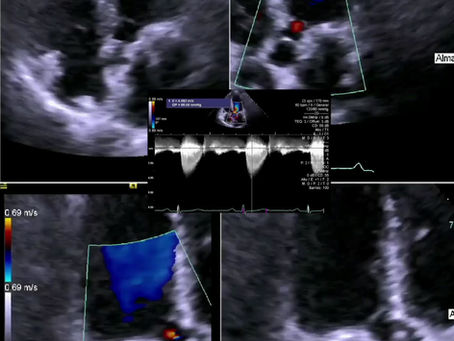

¿Qué podemos observar en el siguiente ecocardiograma con contraste?

¿Qué complicación de endocarditis podemos apreciar en el siguiente caso?